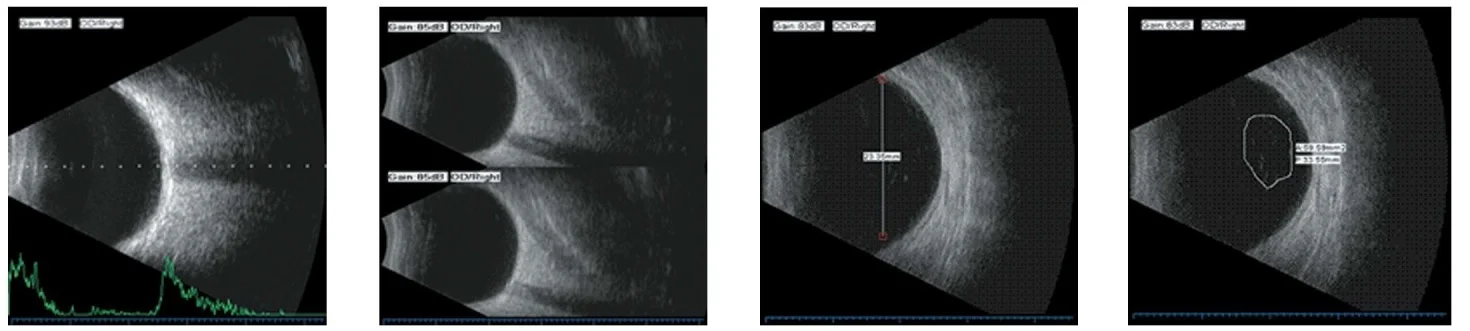

| ផាបញឹកញាប់ | 10MHz / 20MHz (ស្រេចចិត្ត) ជំរុញដោយម៉ាញេទិកគ្មានស្រអាប់ |

| របៀបស្កេន | ការស្កែនក្នុងវិស័យ |

| ដំណោះស្រាយ | ≤0.3មីល្លីម៉ែត្រ; បញ្ឈរ |

| ជម្រៅ: | 60 មម |

| មុំស្កេន | 53 ° |

| ប្រភេទរង្វាស់ | ចម្ងាយឆ្ងាយពហុមុខងារព័ទ្ធជុំវិញនិងតំបន់ |

| រងវាស់ | ជំរៅអង្គជំនុំជម្រះមតិបញ្ជាកម្រាស់កែវពង្រីកប្រវែងរាងកាយប្រវែងប្រវែងសរុបនិងមធ្យម |

| របៀបភ្នែក | PHAKIC / APHAKIC / ក្រាស់ / អ៊ីលផ្សេងៗ |

| រូបមន្តអ៊ីល | SRK-II, SRK-T, HoLOLD-Q, Holladay, Binkhorst-II, Haigis ស្ថិតិ |